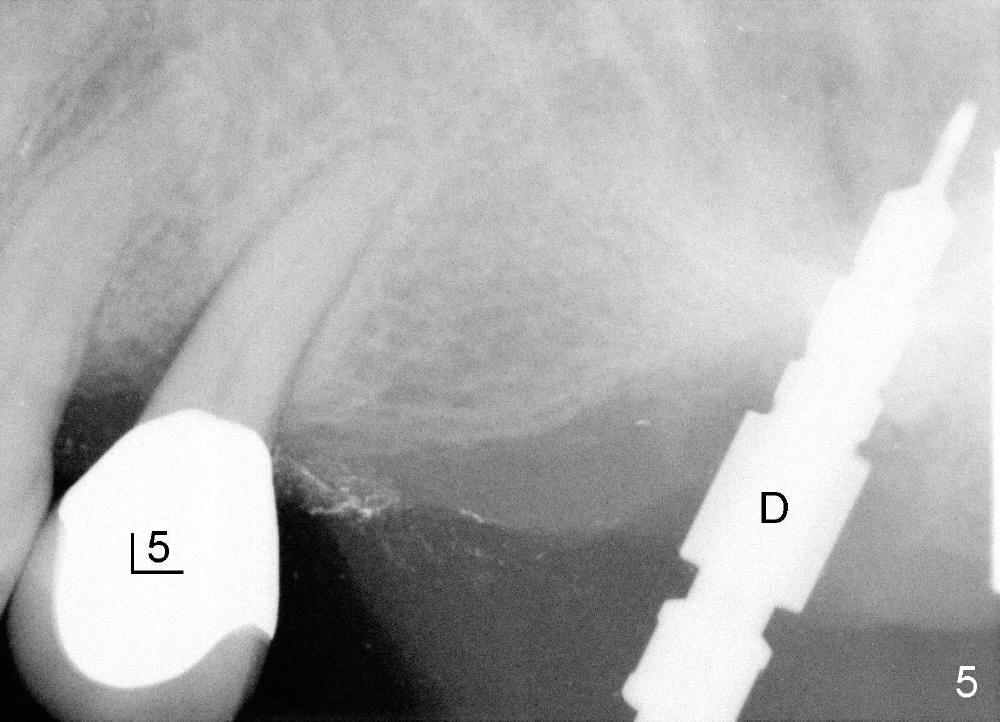

首先在左上五,六号牙之间切断牙桥(图一:黑线),七号基牙比五号松,前者鄂侧牙周袋深,所以对七号牙大刀阔斧,不幸远中颊侧根断裂(图三:离体牙颊侧观;MB:近中颊侧根),可能因为根弯曲,或者死髓牙。图四是离体牙近中观:把断根(远中颊侧根:DB)插回原处,试图把种植体植入三个牙根之间中隔(septum),不过最后种植体主要进入鄂侧根牙槽窝。综合使用骨凿,钻头(图五:D;四点五乘十七毫米)和taps形成植牙窝,当四点五乘十七毫米tap进入植牙窝十四毫米左右,它不稳定,它一定要再深入三个毫米时,才牢靠,似乎非要卡在上颌窦底板最上缘骨皮质中不可。这个现象同样发生在较大taps使用过程中(例如五乘十七,六乘十七,七乘十七毫米)。当七乘十七毫米锥形种植体旋入时(图六:I:植牙;C:喙突),扭力大于六十Ncm。